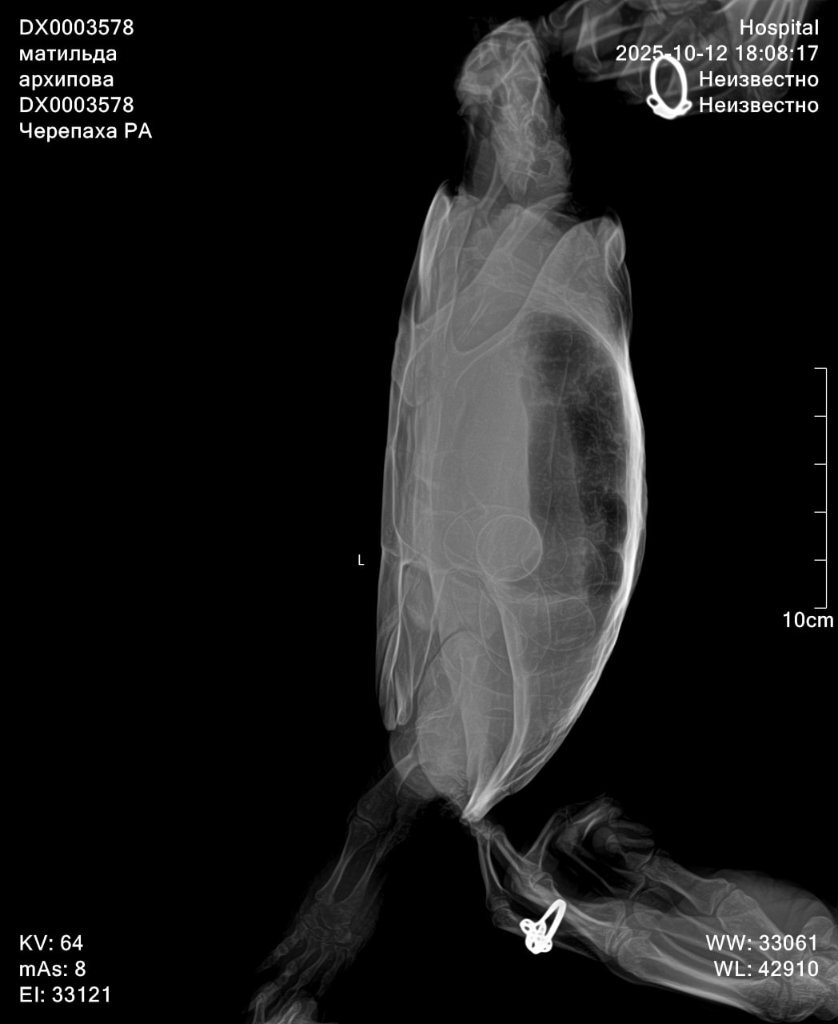

Здраствуйте, сегодня обратилась в другую клинику, прогноз не благоприятный, есть признаки почечной недостаточность, есть переизбыток бактерий в кале, есть признаки стоматита в полости рта. Все это очень и очень плохо. Сделали рентген по направлению, к сожалению описание рентгена рентгенологи сделать не могут, без дополнительной платы. Но завтра я уже записана со снимками на повторный приём. Моя огромная ошибка что ограничилась визитами к одному доктору, и потеряла очень много времени. Тк изначально состояние более стабильное хотябы визуально. Завтра получим назначения от главного врача специалиста по экзотам. Покажу им новые снимки. По фото вроде насчитала тоже количество яиц. Но они значительно сместились, вероятно из-за не к месту сделанного окситоцина